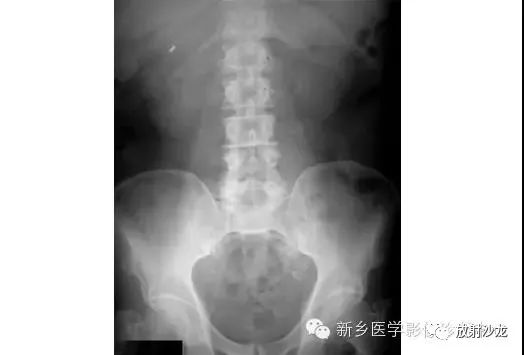

消化道穿孔 = 膈下月牙形游离气体。

急性肠梗阻 = 多个阶梯状液平。

泌尿系阳性结石 = 泌尿系路径上有高密度阴影(亮点)。

注意:

①诊断消化道穿孔时,不要将胃泡影、靠近膈肌下的阶梯状液平等误认为膈下游离气体。阅片时首先找到膈肌,其下的黑色月牙形阴影即为膈下游离气体,此为消化道穿孔的特征性X线表现。膈下游离气体常以右侧明显,左侧被胃掩盖,常不明显。

②正常人也可有少量液平面,因此不能发现液平,就诊断为急性肠梗阻,应结合病史。

③诊断泌尿系阳性结石时,应沿“肾脏→输尿管→膀胱”的径路,在脊柱两旁观察有无高密度亮点。